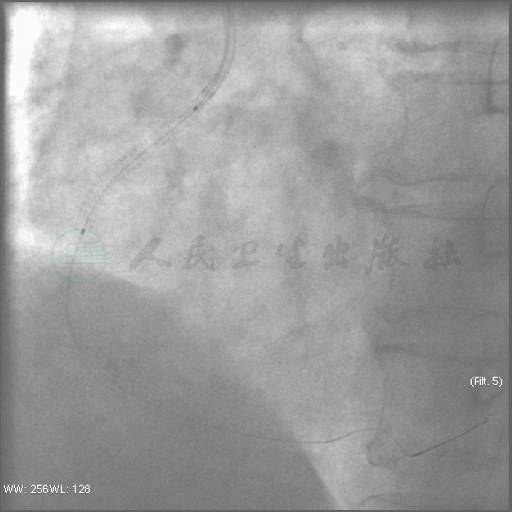

选用6F JR 3.5指引导管送至右冠口,Runthrough导丝到达血管远端,释放Firebird 3.5mm×33mm支架于右冠开口处(图5)。7F EBU 3.5指引导管至左冠口,送0.014′′Runthrough导丝至回旋支远端备用。在微导管的支撑下,Runthrough和Fielder XT钢丝无法通过右冠间隔支侧支至前降支(图6~图8)。

图5 先处理右冠开口病变,支架释放